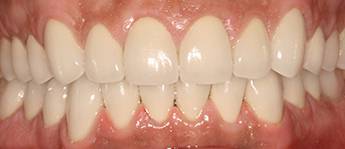

11. eset

27 éves páciensünk egész életében rettegett a fogorvosi beavatkozásoktól. Az összes foga elszuvasodott. A legkárosodottabb fogak gyökérkezelése és a szuvasodásainak megszűntetése után 26 fémkerámia koronát kapott a páciens. Erre a kezelésre is nagyon büszkék vagyunk. 2 hét leforgása alatt sikerült jelentős mértékben javítanunk a páciensünk mosolyán, önbizalmán és mióta velünk talalákozott, már a fogászati kezelésektől sem fél annyira!